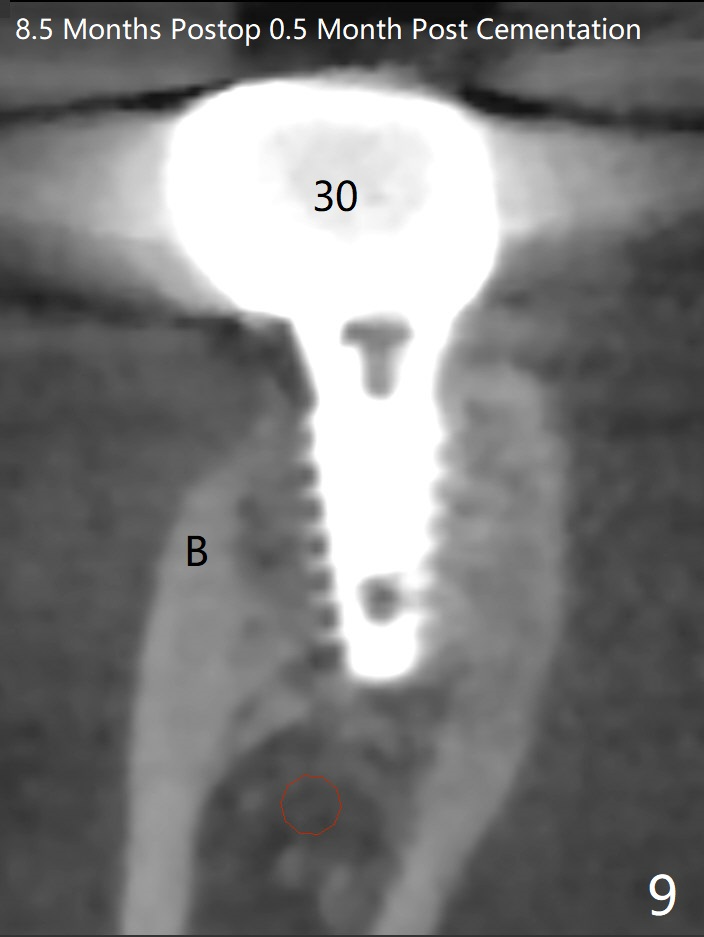

54岁男,右下6,7位点保留后7个月回来植牙,植牙床是个平面(图一),今后两个牙齿之间龈乳头一定缺乏,如何重建?放置导板,稍微使用环形钻头,在6,7植牙床上形成标记(图二),然后切开,植入植体,6扭力低,7高,所以安置愈合(6x5毫米)和修复(5.5x4(4)毫米)基台。原来导板设计把植体植入牙槽嵴(图三:白虚线)下1-2毫米,自动提高植体间牙槽嵴,接着把钻洞产生的骨粉放在后者上缘(*),由近中和远中基台固定。最后覆盖胶原膜,缝合(图四)。原来导板需要切除的角化龈保留住了(图四:7B,7L)。放入修复基台目的是利用它的高度固定牙周敷料。术后3个月7牙槽窝愈合(位点保存后10个月,图五:*),植体间牙槽嵴仍旧高(箭头),6放置修复基台,准备做临时牙冠。右上7反合,需要做局部矫正(图六)。病人非常感激术后三个月制作的临时牙冠(连体)。术后五个月对临时牙冠进行修改:6牙合面垫高(图七:*),这样上下7牙合面分开,上7颊侧放置矫正器,下7牙圈(舌侧有cleat),两者之间安置橡皮筋,上7就可以自由往舌侧移动。术后8.5个月全景片和CT显示植体种植牙槽嵴下(图八至十),这也是重建龈乳头基础。